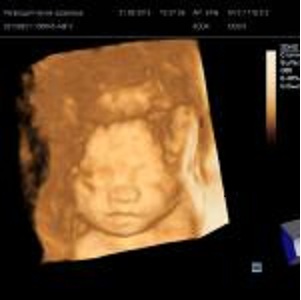

Еще во втором триместре Мы посетили 3Д УЗИ это просто сказка, к слову и обычное УЗИ за 12 лет стало более информативно и картинка стала более отчетливой!!!! Знакомьтесь Федор Николаевич!!!!